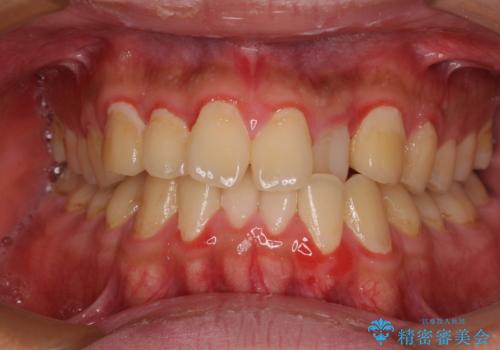

- 前歯のデコボコとクロスバイトを気にして来院された患者様です。

治療開始前は汚れが多く、全体的に歯肉が腫れていましたが、矯正治療を通して腫れも少しずつ改善されました。